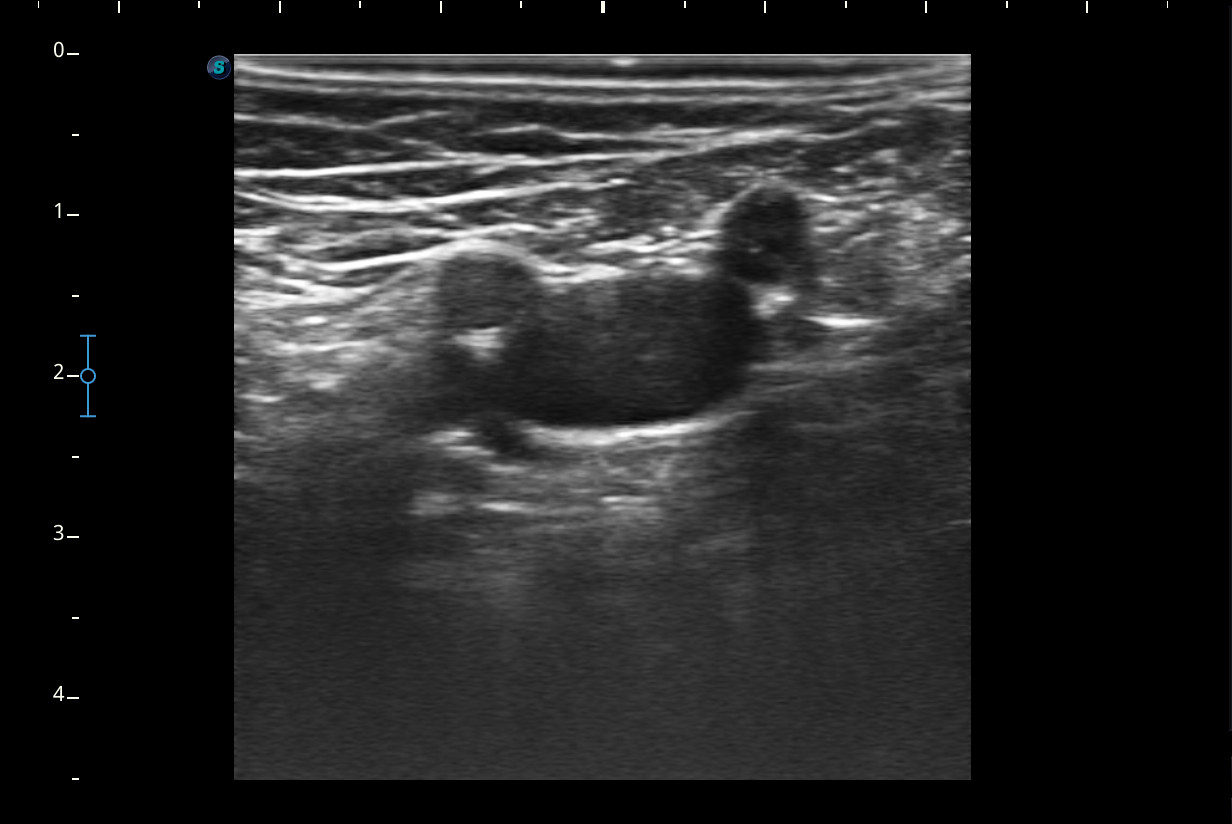

A nivel del hueco poplíteo se visualiza presencia de trombosis de la vena poplítea, no así en localizaciones proximales.Otras pruebas complementarias realizadas (si existen)